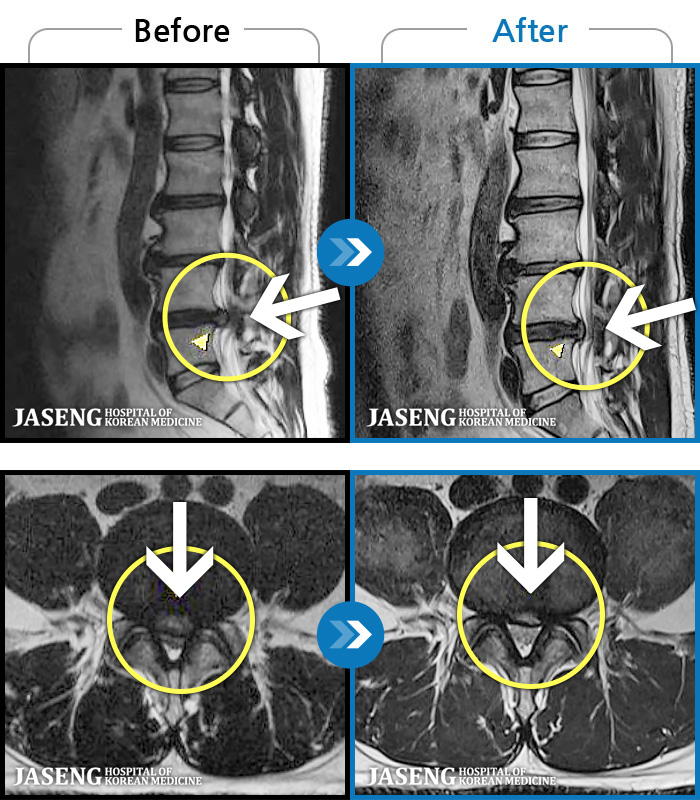

[] 03.04.01~09.11.01

ȯںп Ǹ ǿ ԿǾ, ο ġ ۿ Ƿ ġḦ Ͻñ ٶϴ.